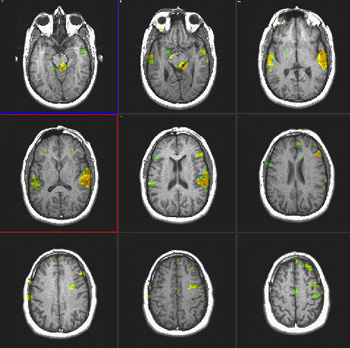

| Activación |

El hemisferio izquierdo muestra activación predominante. Se activaron las siguientes áreas: Área de Broca, porción posterior izquierda de las circunvoluciones temporales inferiores y medias (área 37 de Brodmann), parietal izquierdo y corteza premotora izquierda. Se observa una amplia activación en la cara inferior de los lóbulos occipitales. La activación principal en la derecha está ubicada en la cara inferior del lóbulo frontal (área 11 de Brodmann), un hallazgo observado constantemente en este paradigma. |